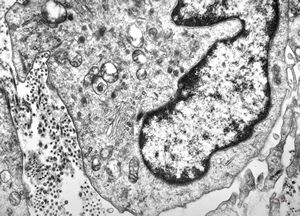

M, 43y. | myeloid leukemia

M, 43y. | myeloid leukemia … Auer bodies

M, 43y. | myeloid leukemia … Auer bodies

M, 43y. | myeloid leukemia … Auer bodies